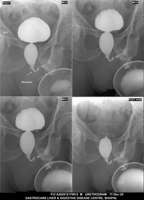

Section: URETHROGRAM Total: 95 images